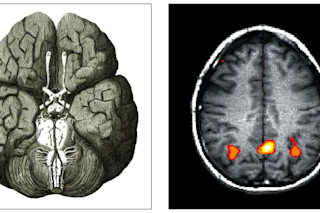

By sheer coincidence (or some journalistic twist of fate) two magazine articles of mine are coming out this week, and they just so happen to make a nice neurological pairing. In Science, I've written an essay about what seventeenth-century natural philosophers have to teach twenty-first century neuroscientists about the brain. In the February issue of Popular Science, my cover story looks at the latest work on brain-machine interfaces that will let people control machines with thought alone. Inevitably, the Pop Sci piece can only focus on a time scale of a few years. But the latest brain-machine interfaces seem to me to be the ultimate incarnation of the dreams of the scientific revolution. Before the 1600s, the world was filled with souls and soul-like forces. In addition to the immortal human soul, there were souls in our organs, in plants, in stars. Water rose in a straw because it abhorred a vaccuum and sought to fill it. In the 1600s, natural philosophers began to dismantle these souls. Galileo busted up the old Aristotelian physics. Descartes offered up the body as an earthen machine. Robert Boyle saw matter as corpuscles--what we call molecules and atoms--colliding and reacting without any purpose driving them from within. Many of these natural philosophers believed that it was essential to take the soul out of nature in order to save Christianity from pagan alternatives. But they also believed that doing so would let mankind master nature. If nature was made up of blind matter that was obedient to God's laws, then unlocking those laws through observation and experiment would turn the world into a scientific paradise of riches and health. This philosophy had one particularly troubling aspect: how did the human mind fit into the world? Was it also just matter in motion? Thomas Hobbes was happy to say it was. Others didn't want to be mistaken for atheists.Boyle's friend Thomas Willis used the priniciples of the scientific revolution to get the first good understanding of the brain, which he envisioned as a chemical engine of memory, perception, and emotions. Today this approach to nature has given rise to, among other things, brain-machine interfaces. If, as promised, they someday give paralyzed people some measure of control, they will be yet another example of promoting health through the mastery of nature. But the remarkable thing is what is being mastered here. As one of the bioengineers I spoke to pointed out, he and his colleagues don't see the brain as some mysterious organ, but as a very complicated digital device that is sending out a series of 1s and 0s. By reading the code, they can do something with it. The brain itself--complete with its intentions and plans--has become yet another natural thing to be harnessed. In my opinion, this is both thrilling and terrifying. I've posted the text and the pdf version of my Science essay on my web site. The table of contents for the February issue of Popular Science is online, but they haven't posted the articles yet. When I get some time, I'll put the text on my site and update this post with the link.